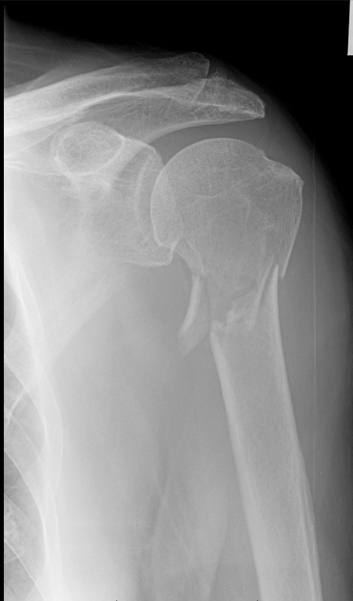

A 44 year old male presents to the ED after getting in a gang fight. He says he was hit just above the elbow with a baseball bat. His x-ray is shown below. What motor tests could you do to assess if nerve damage has also occurred?

The median nerve is subject to injury in this case. You could test thumb abduction, extension and opposition. You could also test wrist flexion and flexion of the index and middle fingers. You should also test for sensory deficit in the distribution of the median nerve.